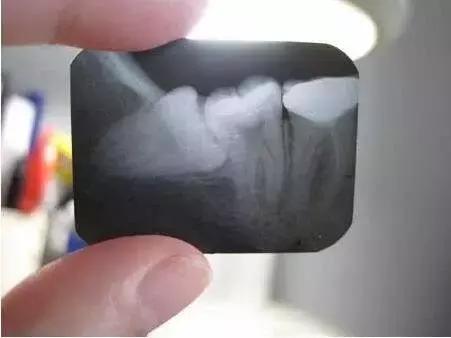

4、 会影响其他牙齿龋坏:阻生智齿能使第二磨牙龋坏。向前倾斜的智齿,其牙冠顶在前牙的颈部,这两颗牙之间形成一个滞留区,由于食物残渣的滞留,得不到正常清洁,细菌繁殖产酸,腐蚀牙齿,导致第二磨牙牙颈容易发生龋齿,往往就诊时已不能保留,需要拔除。